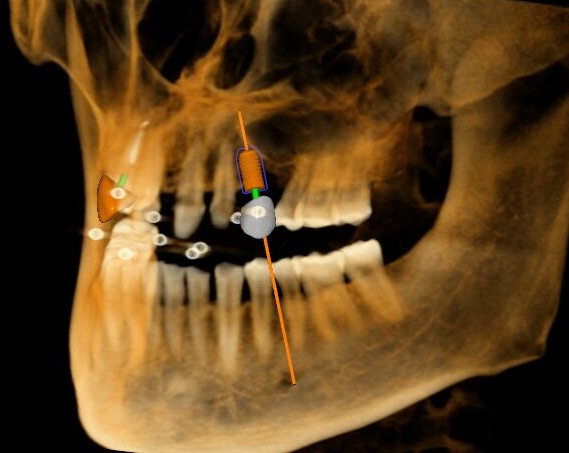

三維視圖

根據(jù)患者CT顯示,使用種植導(dǎo)航軟件設(shè)術(shù)前手術(shù)方案??紤]到患者拒絕手術(shù)摘除上頜竇囊腫等因素,此次手術(shù)選用了Straumann骨水平4.10*8.0mm的植體,植體末端位點(diǎn)設(shè)計(jì)距上頜竇底壁2mm處的同時(shí)兼顧種植方向和修復(fù)間隙,來(lái)達(dá)到理想的效果。